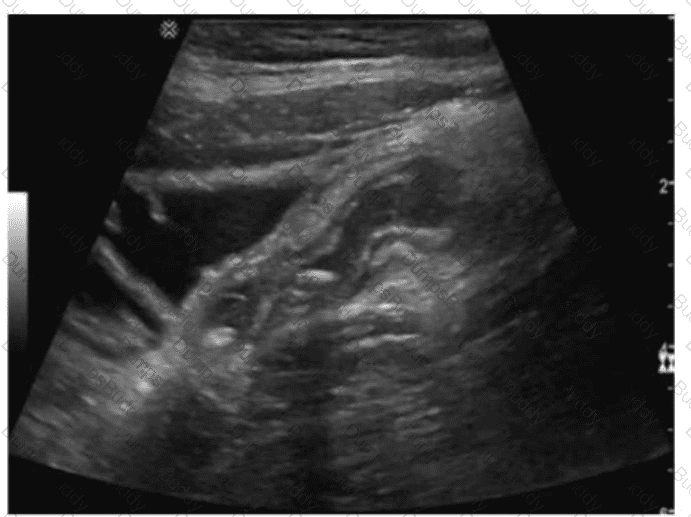

Which vascular condition is most likely associated with the sonographic findings demonstrated in this image?